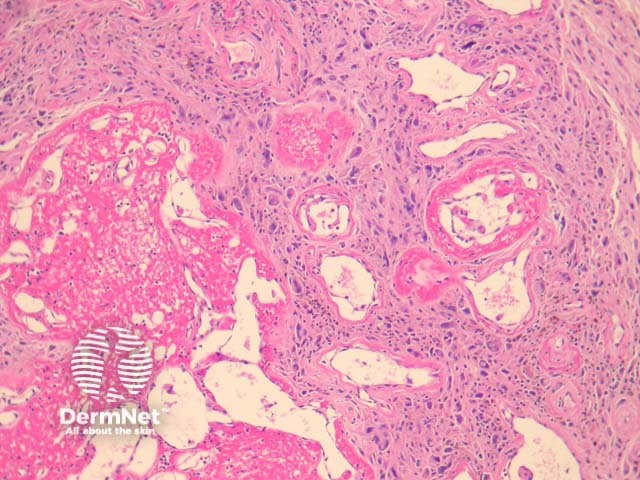

Microscopically, PHAT is characterized by thin-walled, hyalinised and dilated blood vessels (figures 1, 2). Surrounding these is a stroma containing tumour cells which are plump spindled or ovoid cells with pleomorphic nuclei and occasional nuclear pseudoinclusions (Figures 2-3). Mitotic figures are rarely found. There may be extensive hemosiderin deposition (figure 3).

Figure 1

Figure 2

Figure 3